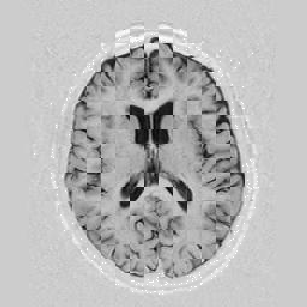

Another larger group of experiments enabled me to study the effects of multi-scale NRR. The results are shown in the form of chequerboard images in Figure [*]. In terms of resolution levels, higher numbers mean that the images are coarser.

Figure: Multi-scale NRR (increasing resolution). From left to right, top then bottom:before NRR; after 5 iterations of NRR at level 2 (higher is coarser); after another 5 iterations of NRR at level 1.